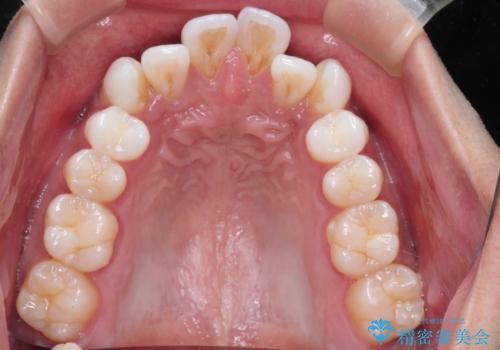

治療完了後、重なり合っていた歯はきれいに整い、懸念されていた前歯の突出も一切起こることなく、理想的な噛み合わせを実現しました。装置が目立ちにくかったため、治療期間中も周囲の目を気にすることなく、前向きに治療に取り組んでいただくことができました。